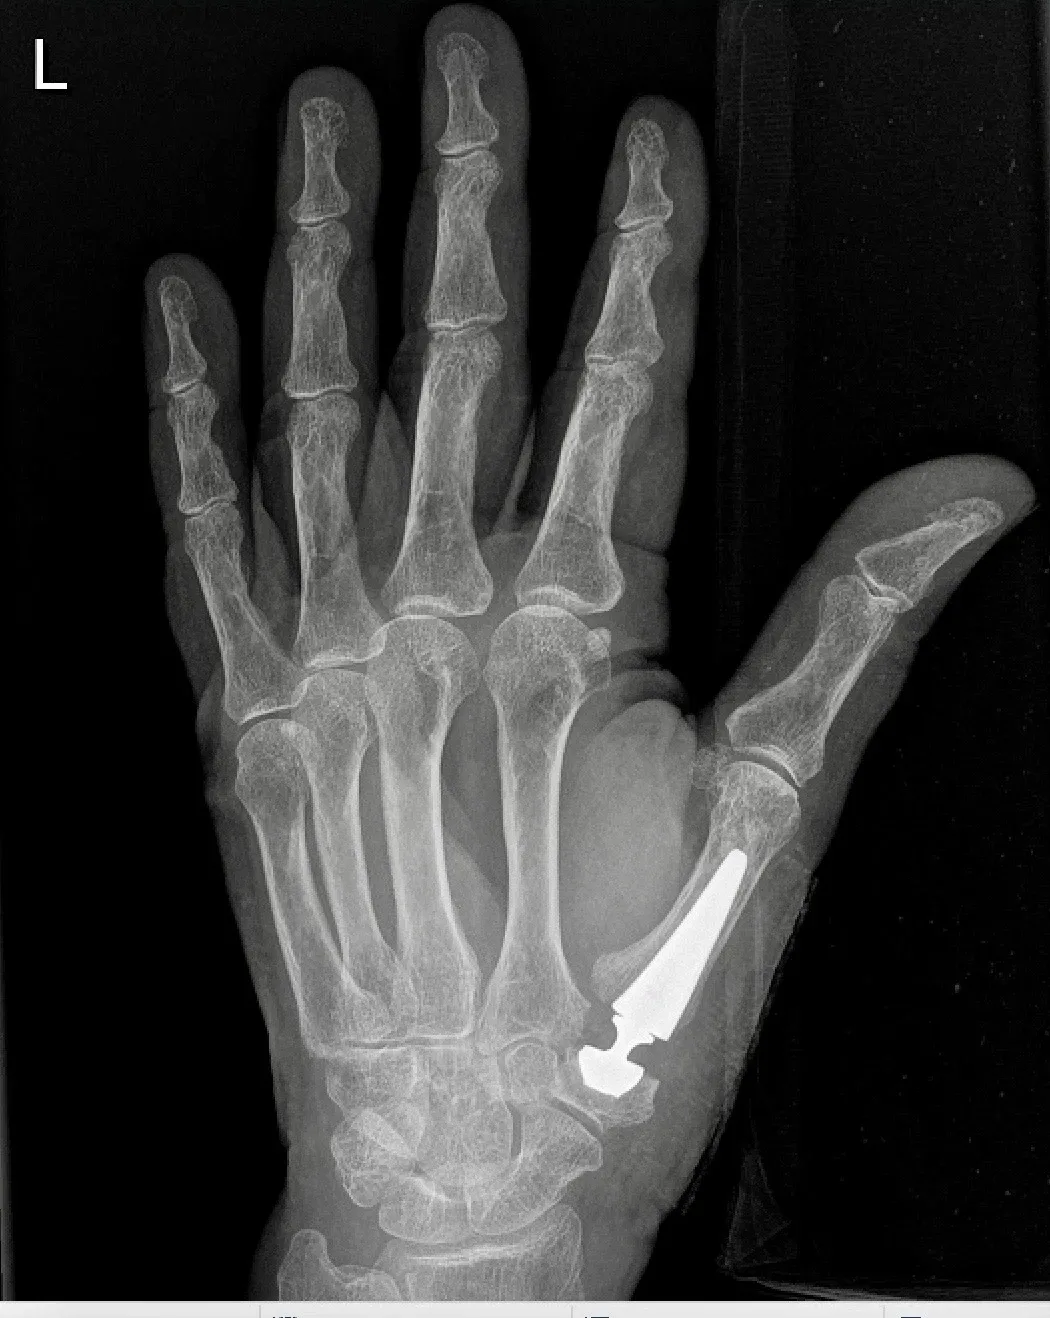

Duimbasisartrose

Wat is het?

Bij duimbasisartrose slijt het kraakbeen in het gewricht tussen het os trapezium en de eerste metacarpaal. Hierdoor bewegen de botten niet meer soepel en ontstaat pijn.

Chirurgisch

- Bij gevorderde artrose of blijvende klachten:

- Duimbasisprothese

- Snelle revalidatie

- Goede pijnverlichting en beweeglijkheid

- Kans op loslating/slijtage is klein

- Indien een prothese niet mogelijk is:

- Andere technieken zoals een Burton-Pellegrini, andere prothesetypes of artrodese

- Ingrepen gebeuren ambulant, meestal onder plexusverdoving